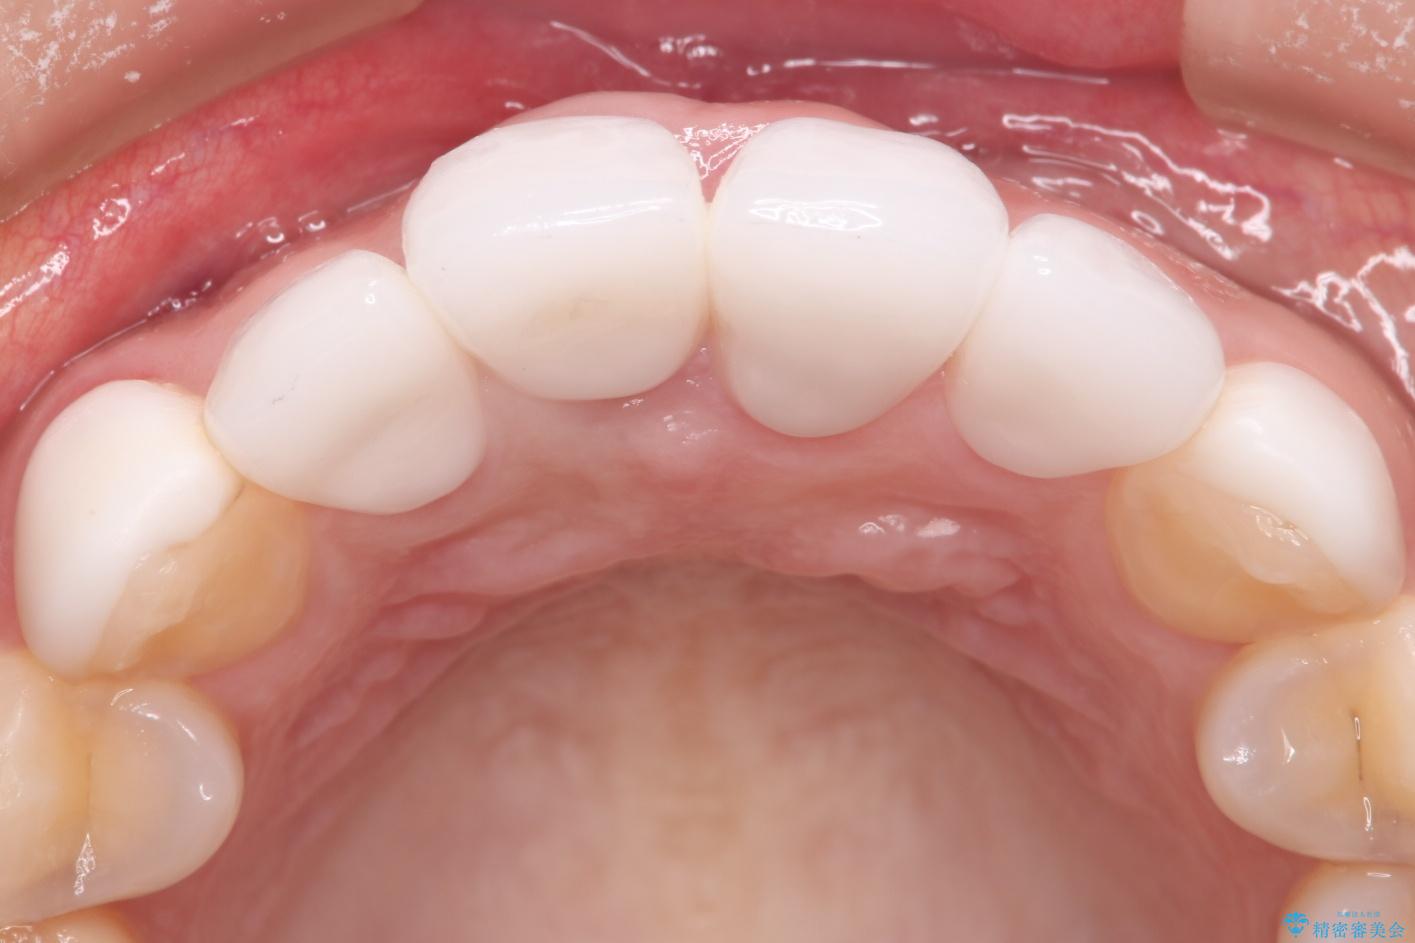

- 他院で治療した前歯の色が気になるということで来院された患者様です。前歯に色の差があり、レントゲンから内部にう蝕も見られたため、審美性に優れ、う蝕になりにくいオールセラミッククラウンで治療いたしました。

清掃性も上がったおかげで、歯肉の状態も良好に保てています。

色の調和もとれたので非常に満足いただけました。